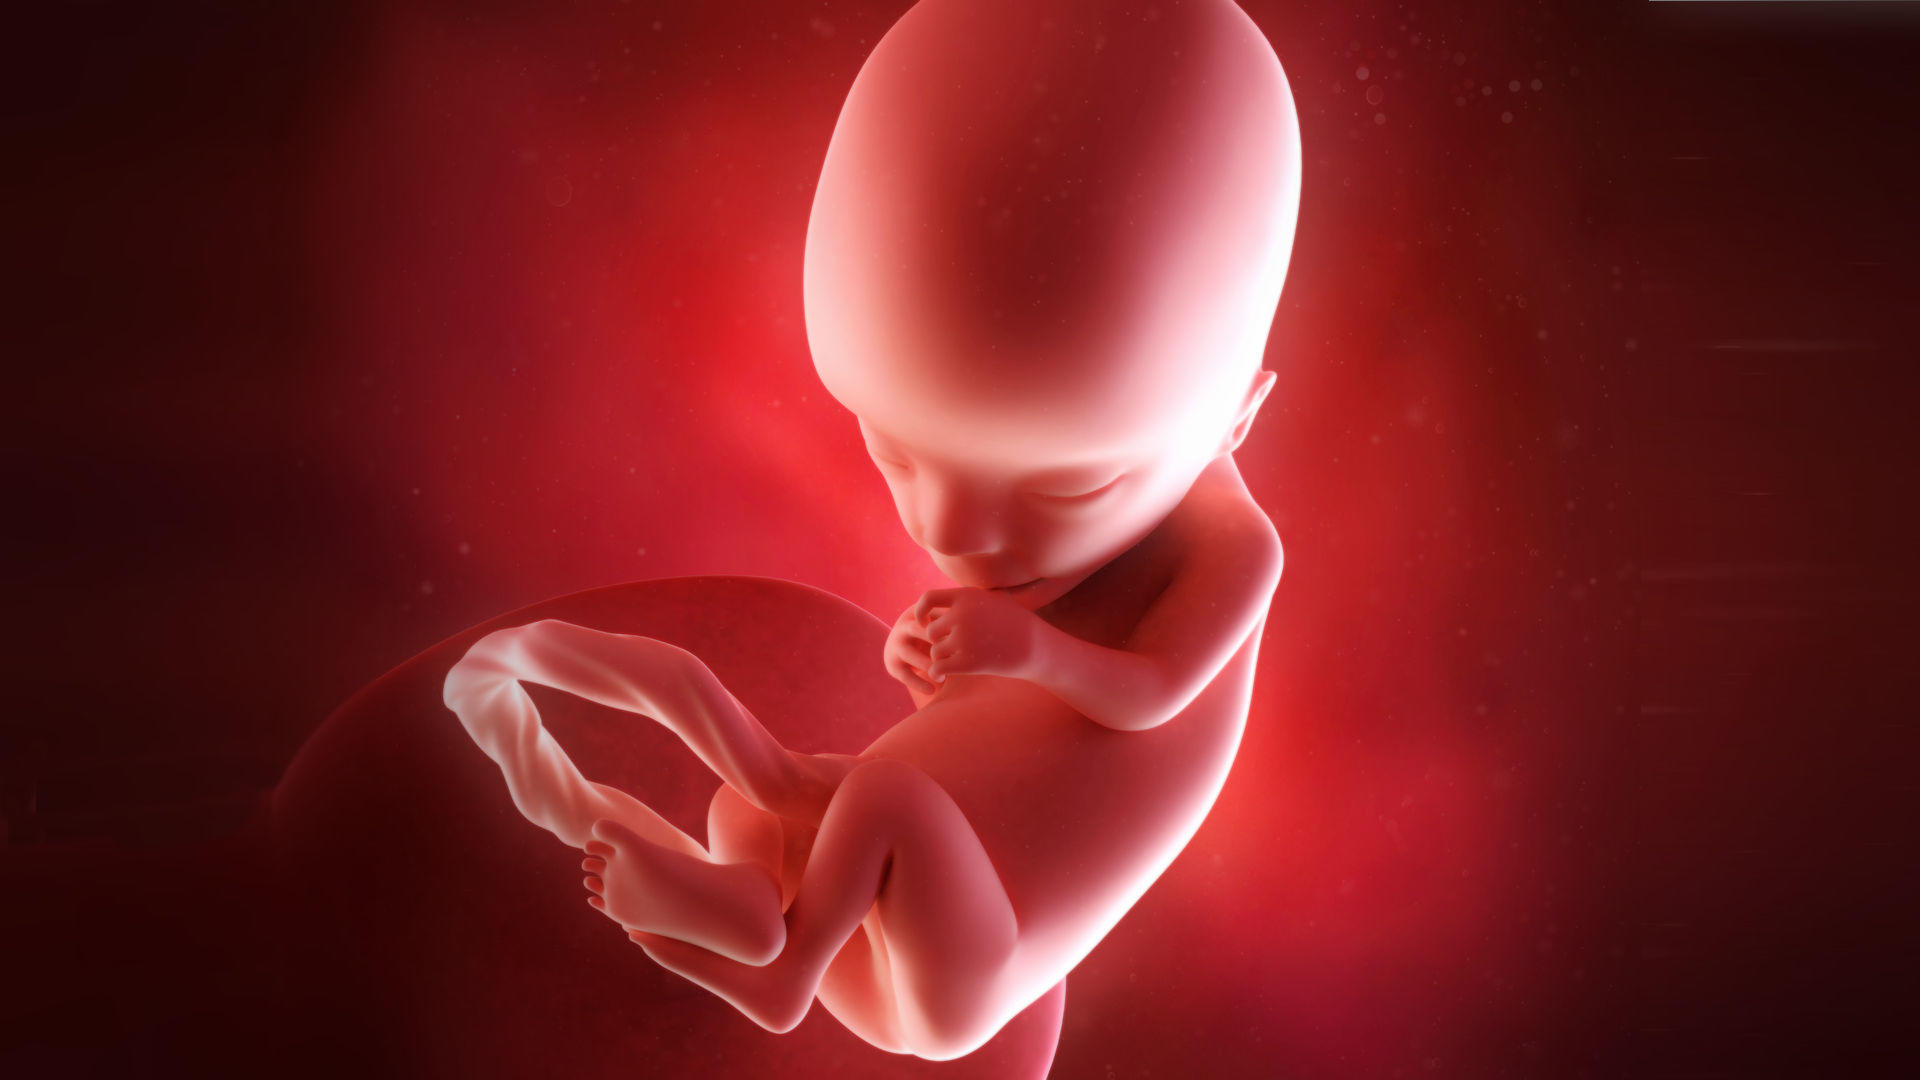

147 неделя

147 неделя 112 фотографий